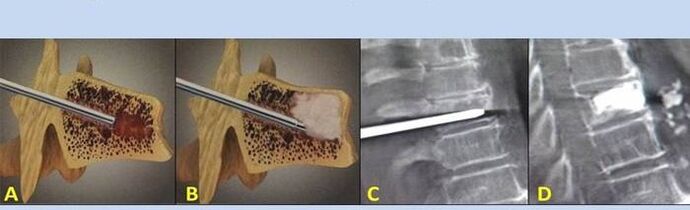

- Nucleoplasty- Removal of the core of the intervertebral disc.The operation relieves pressure on the nerve endings.

- Storm puncture- The method of stabilizing the vertebrae.During the procedure, the doctor fills the cavities of the spine with bone cement.